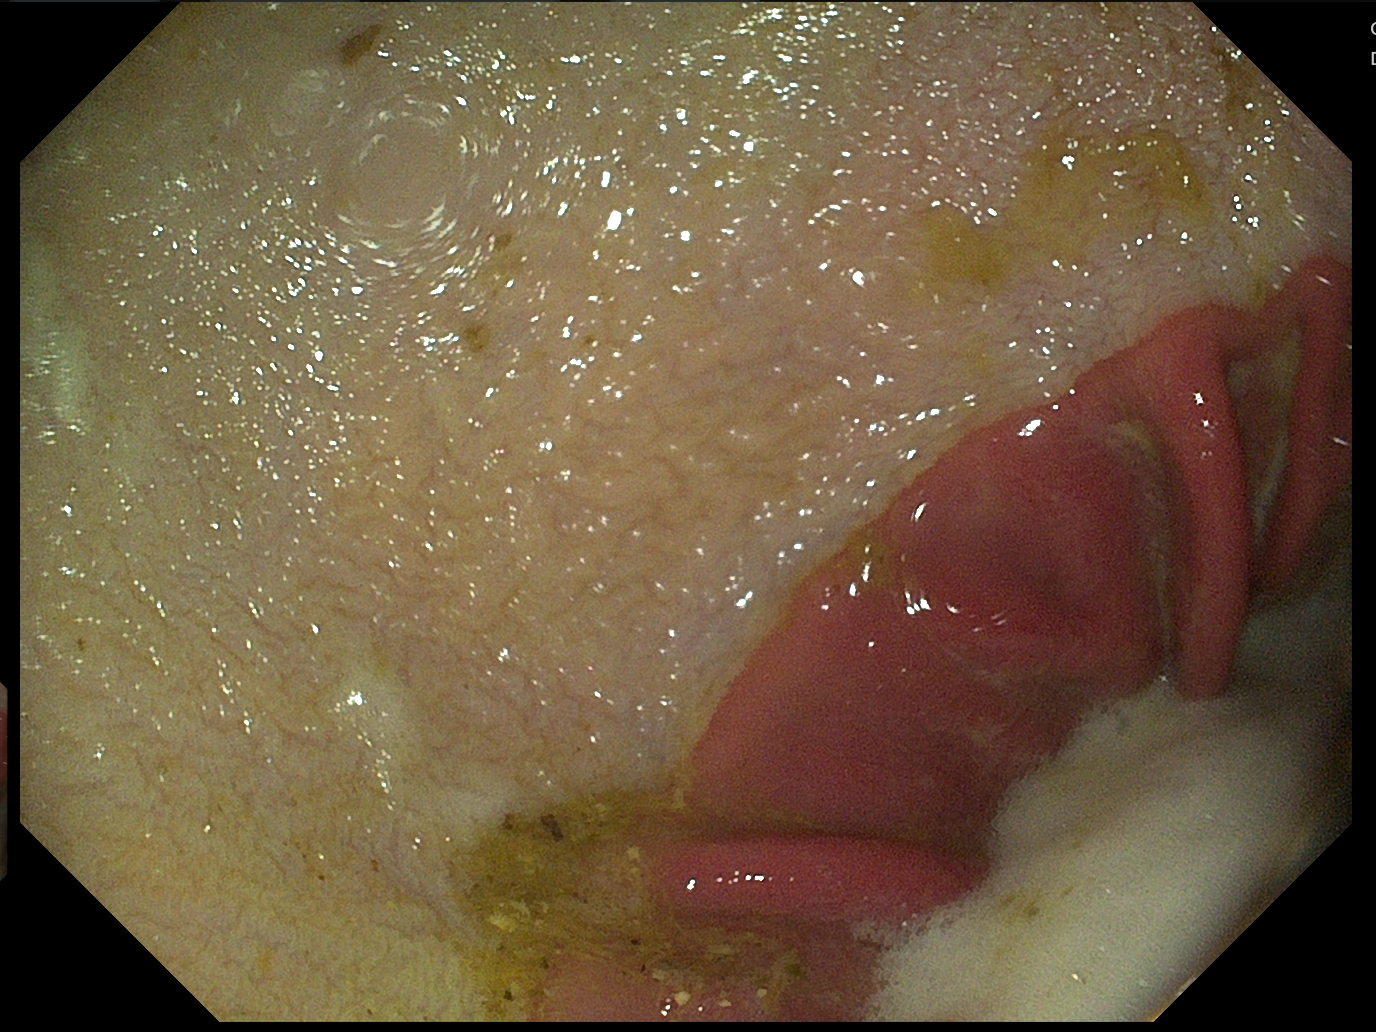

Día 0

• Lesiones en mucosa aglandular (ESGD), grado 2/6

• Sin lesiones en mucosa glandular (EGGD), grado 0/6